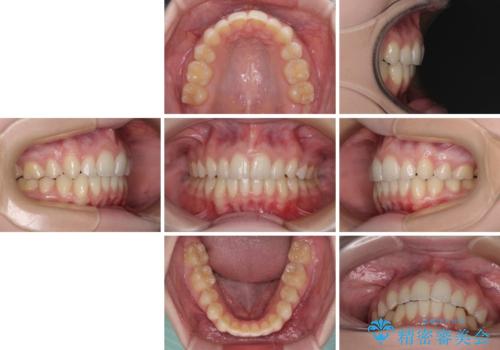

八重歯を短期間で改善 ワイヤー装置による抜歯矯正

下顎の骨格的なズレが大きかったため、上下歯列のバランスが取れるか心配でしたが、上下ともに左右対称に近い歯列で治療を終えることができました。